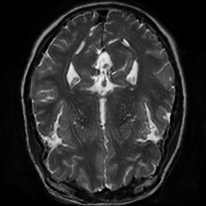

4.4 Qualitative Evaluation

In Figure 5 we analyze the prediction quality of our and compared approaches in a qualitative way. Considering modality propagation in MRI, we see that usage of uncertainty-aware patch invariance (UAPI) gives a better detailed weighting of the cerebrospinal fluid in the middle of the brain. In general, employing patch invariance yields better preservation of fine structures. This observation also applies to accelerated MRI enhancement. In particular, CUT and UAPI provide comparatively sharper knee images with more high-frequency details than the other methods.